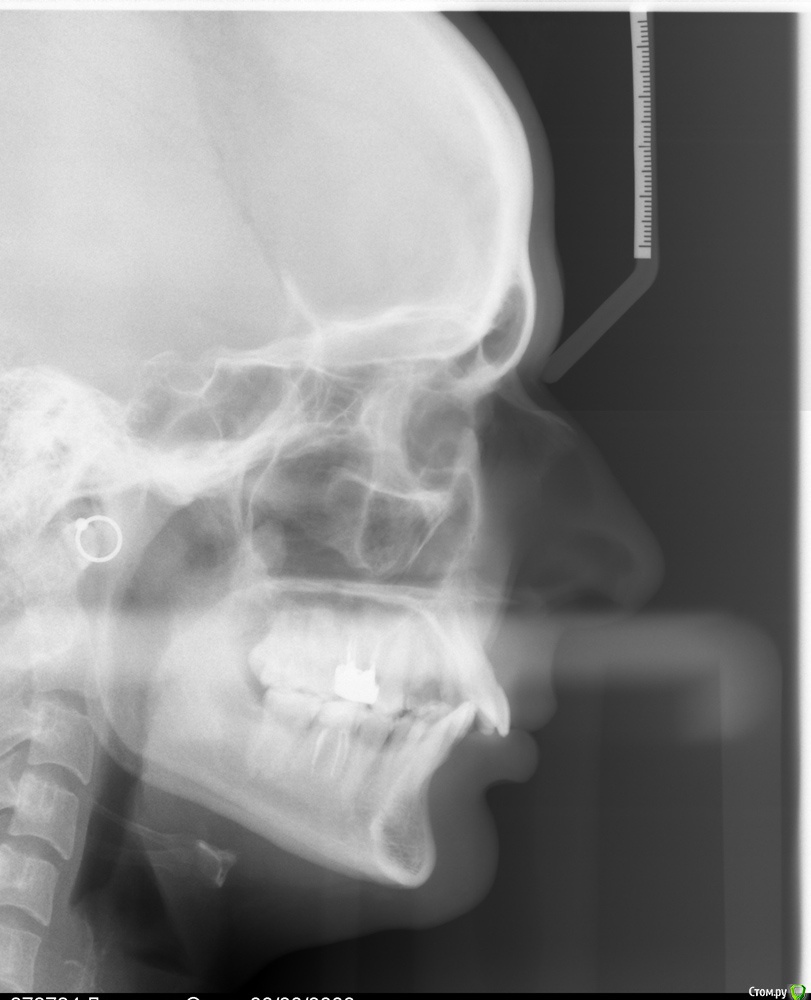

лягушка Опубликовано 11 декабря, 2015 Поделиться Опубликовано 11 декабря, 2015 Добрый день! Давно мучаюсь с проблемой зубов. Не могу принять решение - снесла мозг мужу и врачам. Хочу красивую улыбку. Проблемы -глубокий дистальный прикус, отсутствие 4ке и 6ке. 30 лет. Меня беспокоит отсутствие 4ке. Не сильно - отсутствие 6ке. Не правильный прикус не вызывает недовольство и комплексов. Многие говорят, что у меня красивая улыбка. Внешность полностью устраивает. Врачей волнует мой не правильный прикус. Итак, я уже слышала много мнений и очень разных. Как я поняла у меня три варианта. 1. Идеальный. Брекеты. Удаление 4ке. Операция. На этот вариант я не готова. Только если она жизненна необходима. 2. Компромисс. Удалять 4ку и возможно снизу еще два. Ставить брекеты. Далее имплантация на 8ку. Этот вариант меня смущает тем, что как я понимаю прикус мне он правильным не сделает да? зубы у меня будут ровнее. Но к ним у меня нет претензий. Я не могу понять лечение на брекетах будет лучше для здоровья моих зубов или просто поставит зубы в соответствии с нормами медицины. Так же по мнение врача ухудшиться внешний вид (так как зубы уйдут назад) возможно увеличение нижней губы. 3. Творческий))) Оставить свой прикус и в покое. Поставить имплант на 4ку. И чуть дорастить с помощью пломбы 5ку. Склоняюсь к нему. Но боюсь что будет дальше. Не будет ли это бомба замедленного действия- начнутся проблем с челюстью или зубами. Придется вырвать имплант и ставить таки брекеты. . Какие прогнозы на будущее?? Возможно ли дожить после брекетов со своими зубами до старости? Просто смысл их выравнивать если к годам к 50 придется менять на новые? Про лицо - если ставить брекеты это уменьшит или увеличит носогубную складку? Спасибо. Извините ))Всем лучик счастья) http://s018.radikal.ru/i524/1512/d0/4f17709addaat.jpghttp://s001.radikal.ru/i195/1512/a9/cc8180641ff4t.jpghttp://s020.radikal.ru/i721/1512/d9/75ef41300d90t.jpg http://s019.radikal.ru/i641/1512/c7/e1ff9243fe2ft.jpg http://s017.radikal.ru/i422/1512/dc/38aeb2319878t.jpg http://s017.radikal.ru/i407/1512/7f/2a9905741d88t.jpg Ссылка на комментарий